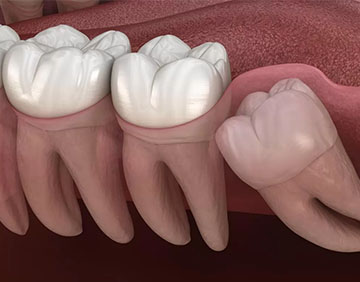

Gömülü Diş Tedavileri

Gömülü dişler hastanın beslenme fonksiyonlarını etkileyecek bir bölgede veya diş ve yüz estetiğini olumsuz yönde etkileyecek durumdaysa, mutlaka ortodondik açıdan değerlendirilerek tedavi edilmelidir. Böylece gömülü dişle ilgili yaşanan sorunlar ortadan kaldırılacağı gibi, estetik kaygılar da giderilmiş olacaktır. Gömülü diş ameliyatlarında, dişin yer aldığı bölge lokal anestezi ile uyuşturulmakta, diş etrafındaki kemik kaldırılarak gömülü diş çekilmektedir. Diş çekim yapıldıktan sonra dikiş atılarak yaranın tedavi süreci başlatılır. Yaklaşık bir hafta ile 10 gün sonra dikişler alınarak tedavi sonlandırılır. Ameliyatı gerçekleştiren hekimin gerek görmesi halinde operasyon sonrası ağrı kesici ve antibiyotik tedavisi önerilir. Gömülü diş operasyonlarında hekimin bilgi ve tecrübesi oldukça önemlidir. Ameliyatın başarılı geçmesini sağlayan en önemli unsur, bölgenin anatomisinin iyi değerlendirilmesi ve ameliyat esnasında uygun anestezi uygulanmasıdır. Bu sayede ameliyat sırasında acı hissedilmez.